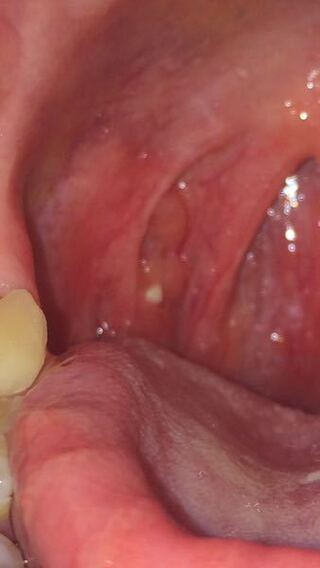

喉 の 奥 口内炎 画像

口内写真あります 喉の奥に口内炎のようなものがいくつもあるのです 眼 耳鼻咽喉の病気 教えて Goo

喉の奥が白いのは口内炎ではなく膿栓だった 口内炎と膿栓を見分ける方法を教えます